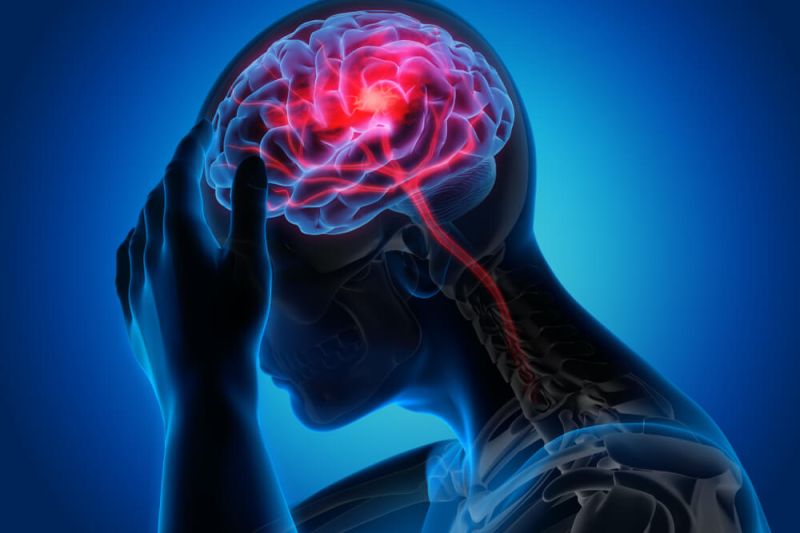

Quais são as possíveis complicações da doença?

As doenças vasculares periféricas podem trazer complicações sérias à saúde e ao bem-estar geral do paciente. Essas complicações podem incluir:

- Infarto;

- AVC;

- Falhas e problemas renais;

- Amputações nos membros inferiores e superiores;

- Morte;